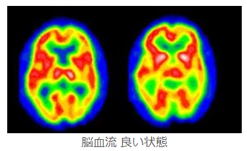

脳は加齢や病気によって機能が低下します。手足の動きが悪くなったり、ボケ症状が進行したり、 目や耳が悪くなったり、さまざまな症状が現れます。 脳の血液の流れが悪くなり、細胞の能力が衰えることが、大きな原因です。

通常の治療法やリハビリで改善しない場合、または早く改善したい場合、 幹細胞を用いたPRP治療・幹細胞治療が新しい治療法として期待できます。